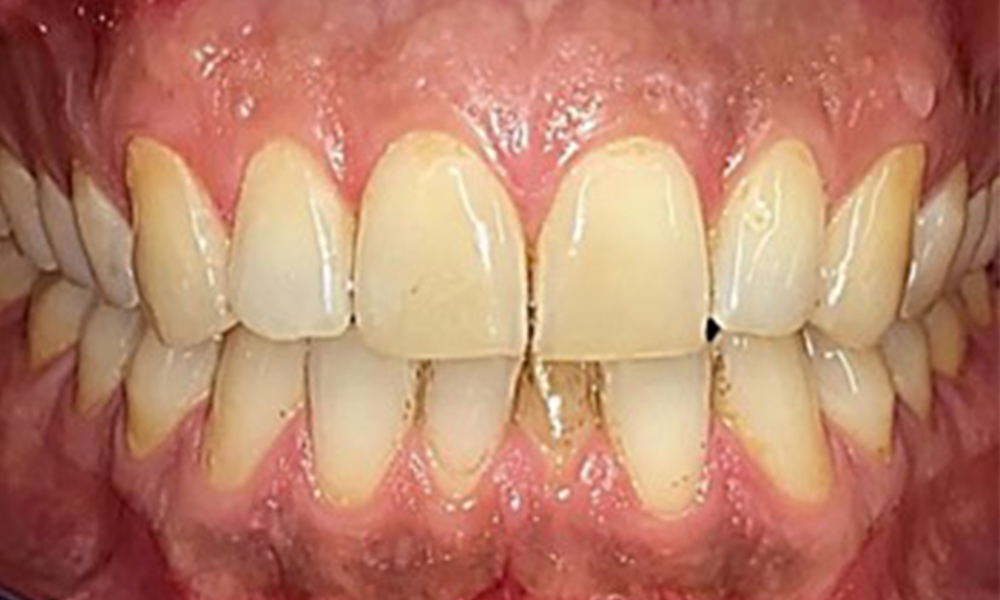

There were no pathological extraoral findings. During intraoral examination, inspection of the frontal view revealed brownish discolouration near the keratinised gingiva and at the transition to the moveable mucosa (Fig. 2), which could be attributed to nicotine consumption. Whitish mucosal lesions were observed on the palate, particularly near the maxillary molar palatal surfaces, indicating increased keratinisation and can also be attributed to nicotine consumption. The tongue was covered with a removable white and brownish coating.

The patient has full dentition with a total of 28 teeth. There were noteworthy erosions and attritions. (Fig. 4, Fig. 5). Due to bruxism, the patient has been wearing a splint with an adjusted bite block at night for many years. The erosions were caused by long-term consumption of isotonic beverages. No periodontal bone loss or active caries were observed.

Instruction and motivation are important components of these appointments. Good home-based intraoral hygiene behaviour and understanding are important for patients. Plaque accumulation is particularly evident in the cervical regions (Fig. 8).